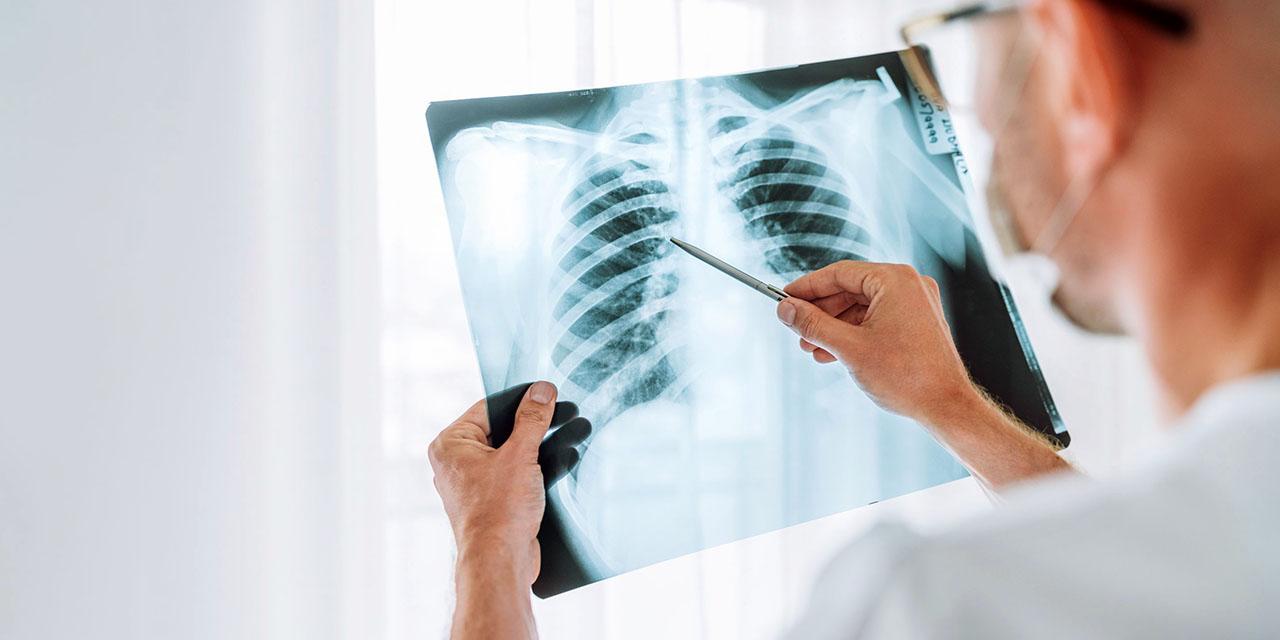

PIEDRAS NEGRAS, COAH.- Actualmente, 29 casos de tuberculosis están siendo atendidos en los seis Centros de Salud de la Jurisdicción Sanitaria Uno de Piedras Negras, informó Priscila Hernández López, coordinadora de Prevención y Promoción de la Salud.

Explicó que los médicos de estos centros identifican a pacientes con síntomas pulmonares sospechosos y los refieren al Centro de Micobacteriosis, donde se les realiza una baciloscopía para confirmar o descartar la enfermedad.

Agregó que durante 2024 se realizaron mil 292 baciloscopías, de las cuales 78 resultaron positivas.